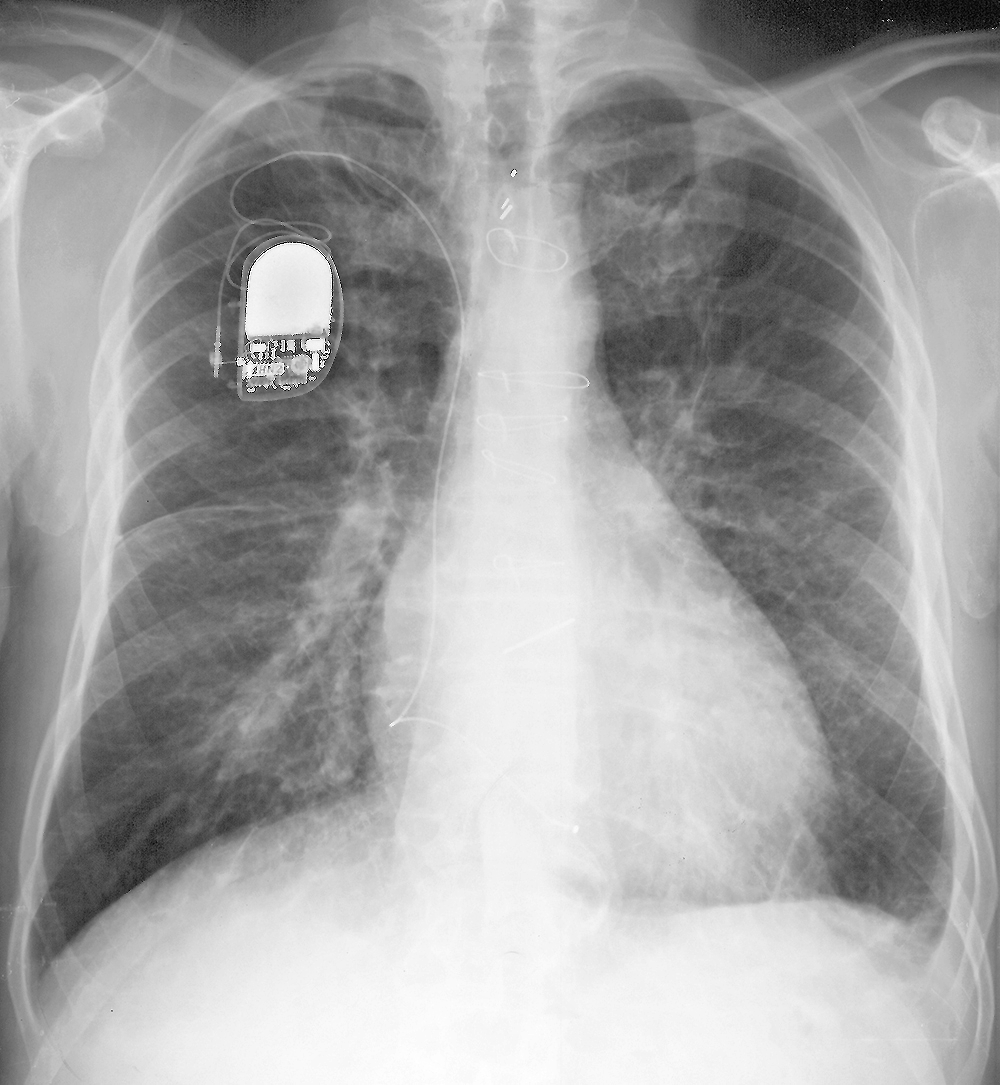

Topic 2

intermediate case CHF

Further Explanation: